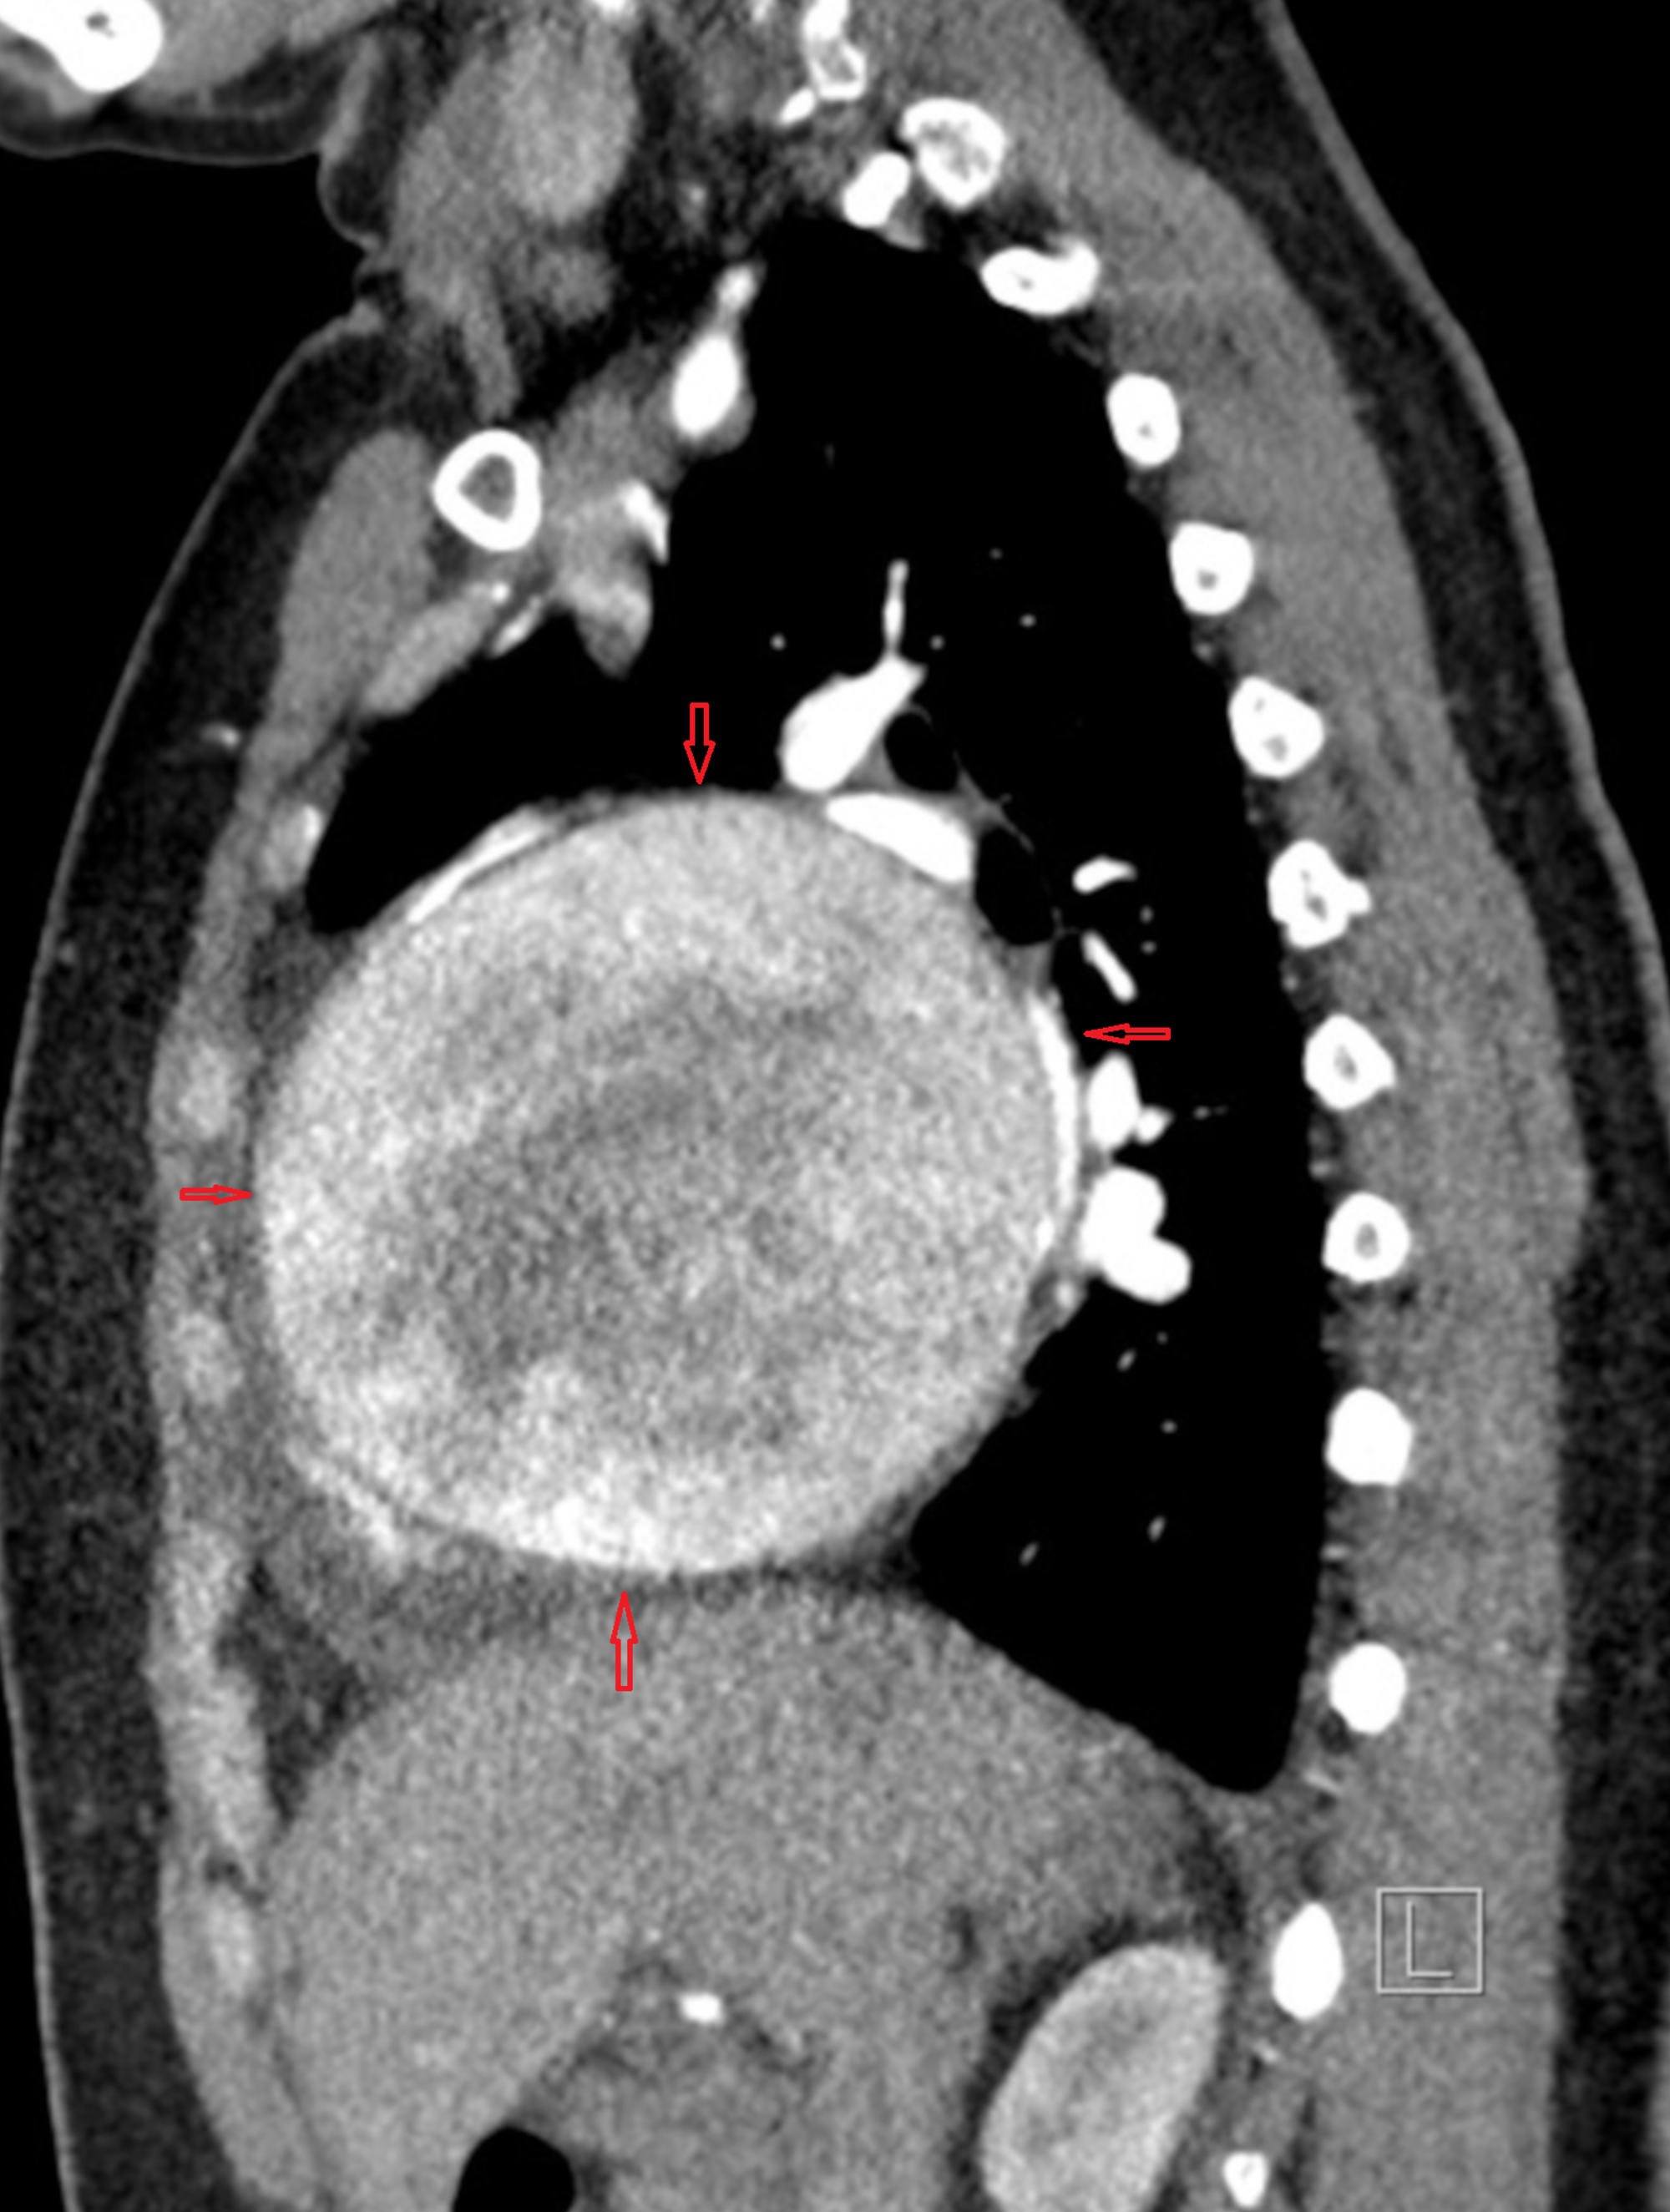

A rapidly focussed TTE usually confirms the diagnosis.TEE might be used but carries a small risk of directly aggravating dissection when performed in an unstable patient. Conventional CT provides good (but limited) information, spiral MDCT delineates the vascular anatomy in a more clear way. MRI probably scores over and adds flow dynamics.

(4D Phase-contrast MRI showing slow helical flow in the false lumen and high-velocity flow in the true lumen. Computational flow dynamics will help assess entry point, plane of dissection, calculate false lumen Index, pressure and wall stress in true lumen and Aortic branch compromise etc . Image courtesy. The Lancet Volume 385, Issue 9970, 28 February–6 March 2015, Pages 800-811)